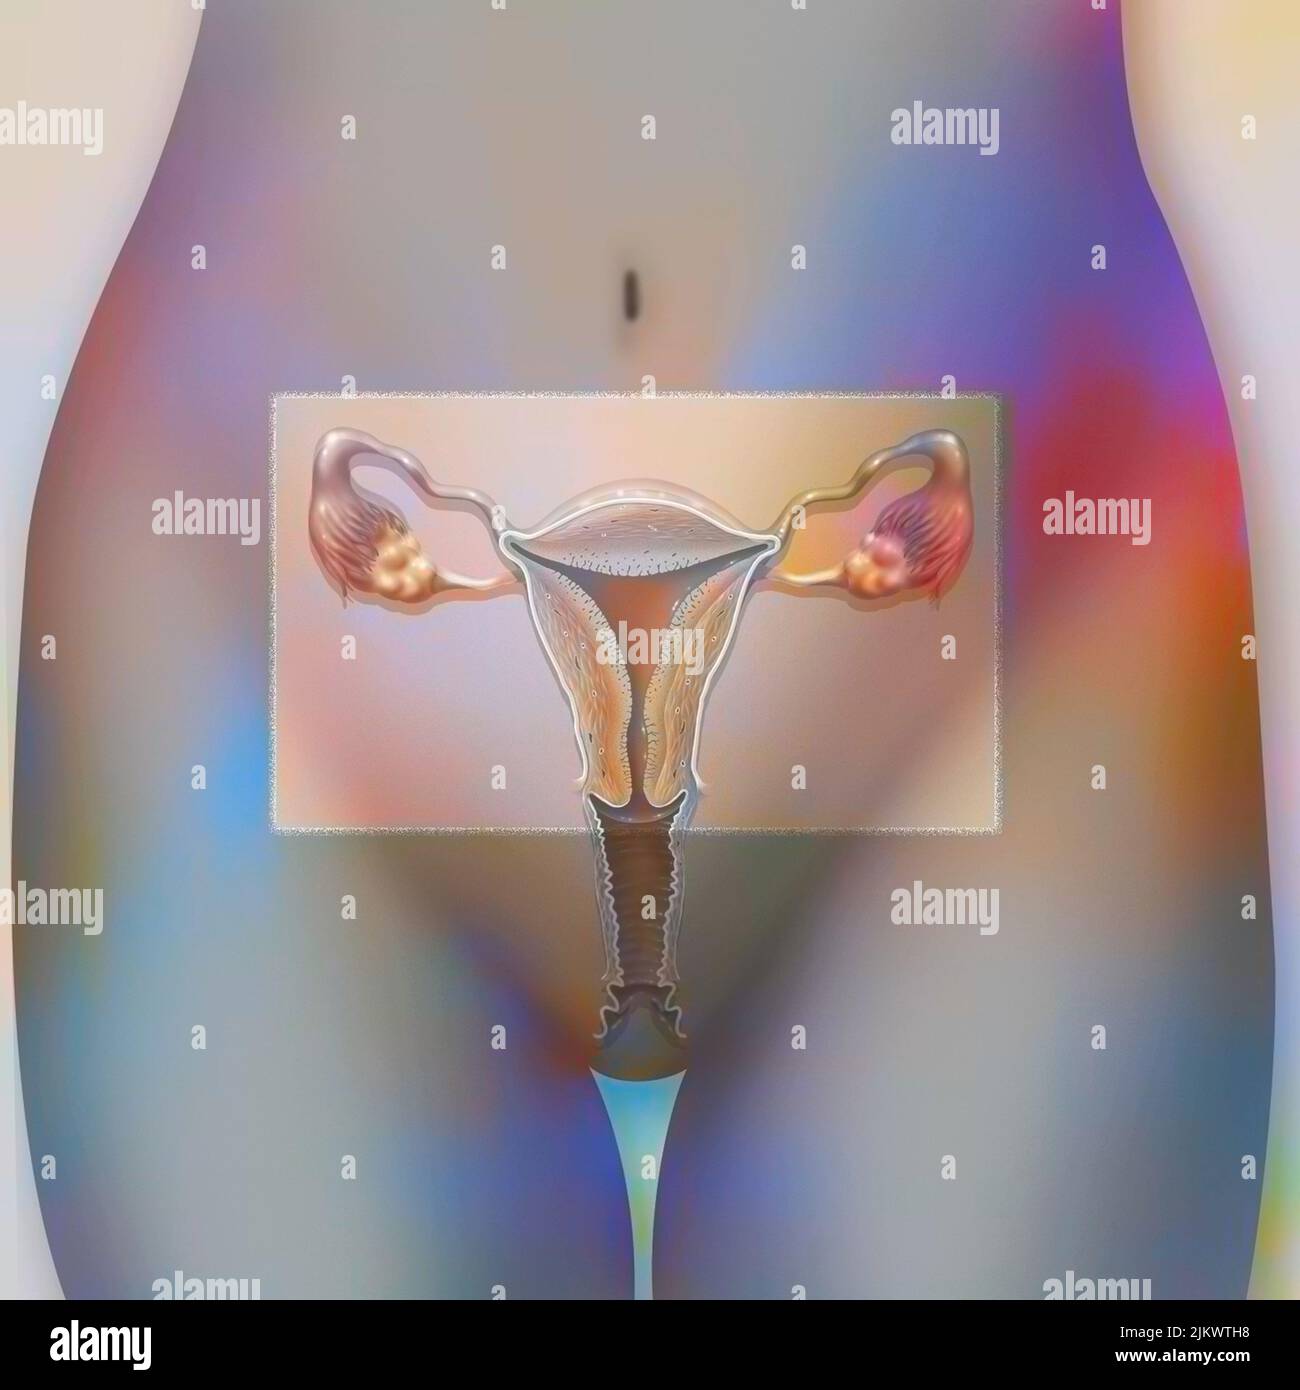

RF2JKWRM1–Vue antérieure des organes génitaux féminins avec vagin, utérus, trompes de Fallope, ovaires.